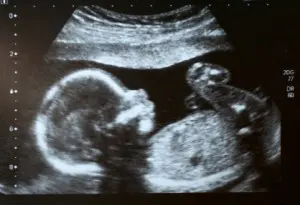

Baby visualized with ultrasound, side profile

Prenatal ultrasounds look for heart problems and other birth defects.